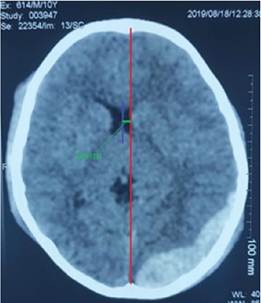

Según la escala de Marshall el paciente presenta una lesión difusa de tipo IV, se aprecia una desviación de la línea media superior a 5 mm (Ver figura 1). En la tomografía se puede observar en la ventana ósea: fractura parietooccipital y en la ventana parenquimatosa una lesión hiperdensa biconvexa que corresponde al hematoma epidural supra e infratentorial que abarca 20 cortes de la tomografía ubicado en la fosa posterior en la región occipital y parietal, las medidas de este hematoma son 10 cm de alto, 8,5 cm de largo y 2,3 cm de ancho (Ver figura 2). Para la estimación del volumen se aplica la Fórmula ABC/2. Donde A corresponde a= longitud máxima de la lesión (en cm) de la TC, B = ancho perpendicular de A en el mismo corte de la tomografía y C = número de cortes multiplicado por el grosor del corte, aplicándolos a nuestros valores tenemos un total de 97,5 ml; es importante entender que el mecanismo provee información crucial para el entendimiento de la lesión. El paciente sufrió una colisión contra el pavimento luego de salir proyectado de su bicicleta, dando una vuelta aproximada de 270° para finalmente impactar con la región occipital en contra de la porción rocosa de la carretera, lo cual nos permite concluir con total seguridad que esta fue la causa del hematoma epidural. Posterior a ello se elaboró un plan de tratamiento en el cual se decide su operación quirúrgica en el tercer día de hospitalización. Para contextualizar el caso: paciente ingresa con un diagnóstico de Traumatismo craneoencefálico moderado con Glasgow: 12/15, Edema Cerebral, Hematoma epidural supra e infratentorial.